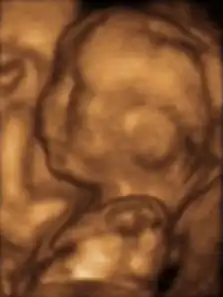

Fetus at 5 months